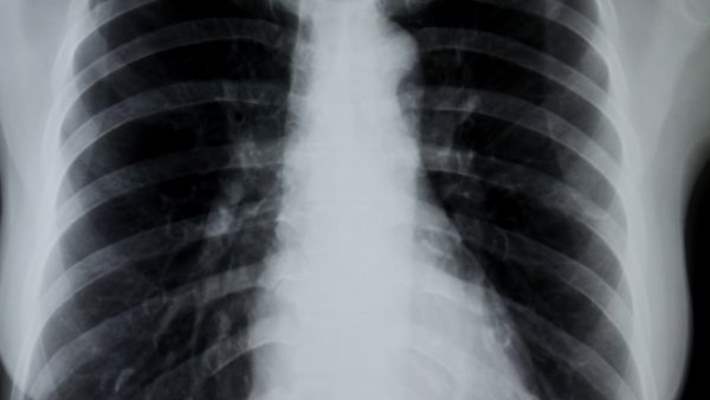

Doktorunuz size belirtileriniz hakkında sorular soracak ve sizi muayene edecektir. Bunlar doktora genellikle akut bronşit olup olmadığını tespit etmek için yeterli bilgi verir. Bazı vakalarda doktor zatürree veya başka bir akciğer probleminin olmadığından emin olmak için göğüs röntgeni isteyebilir.